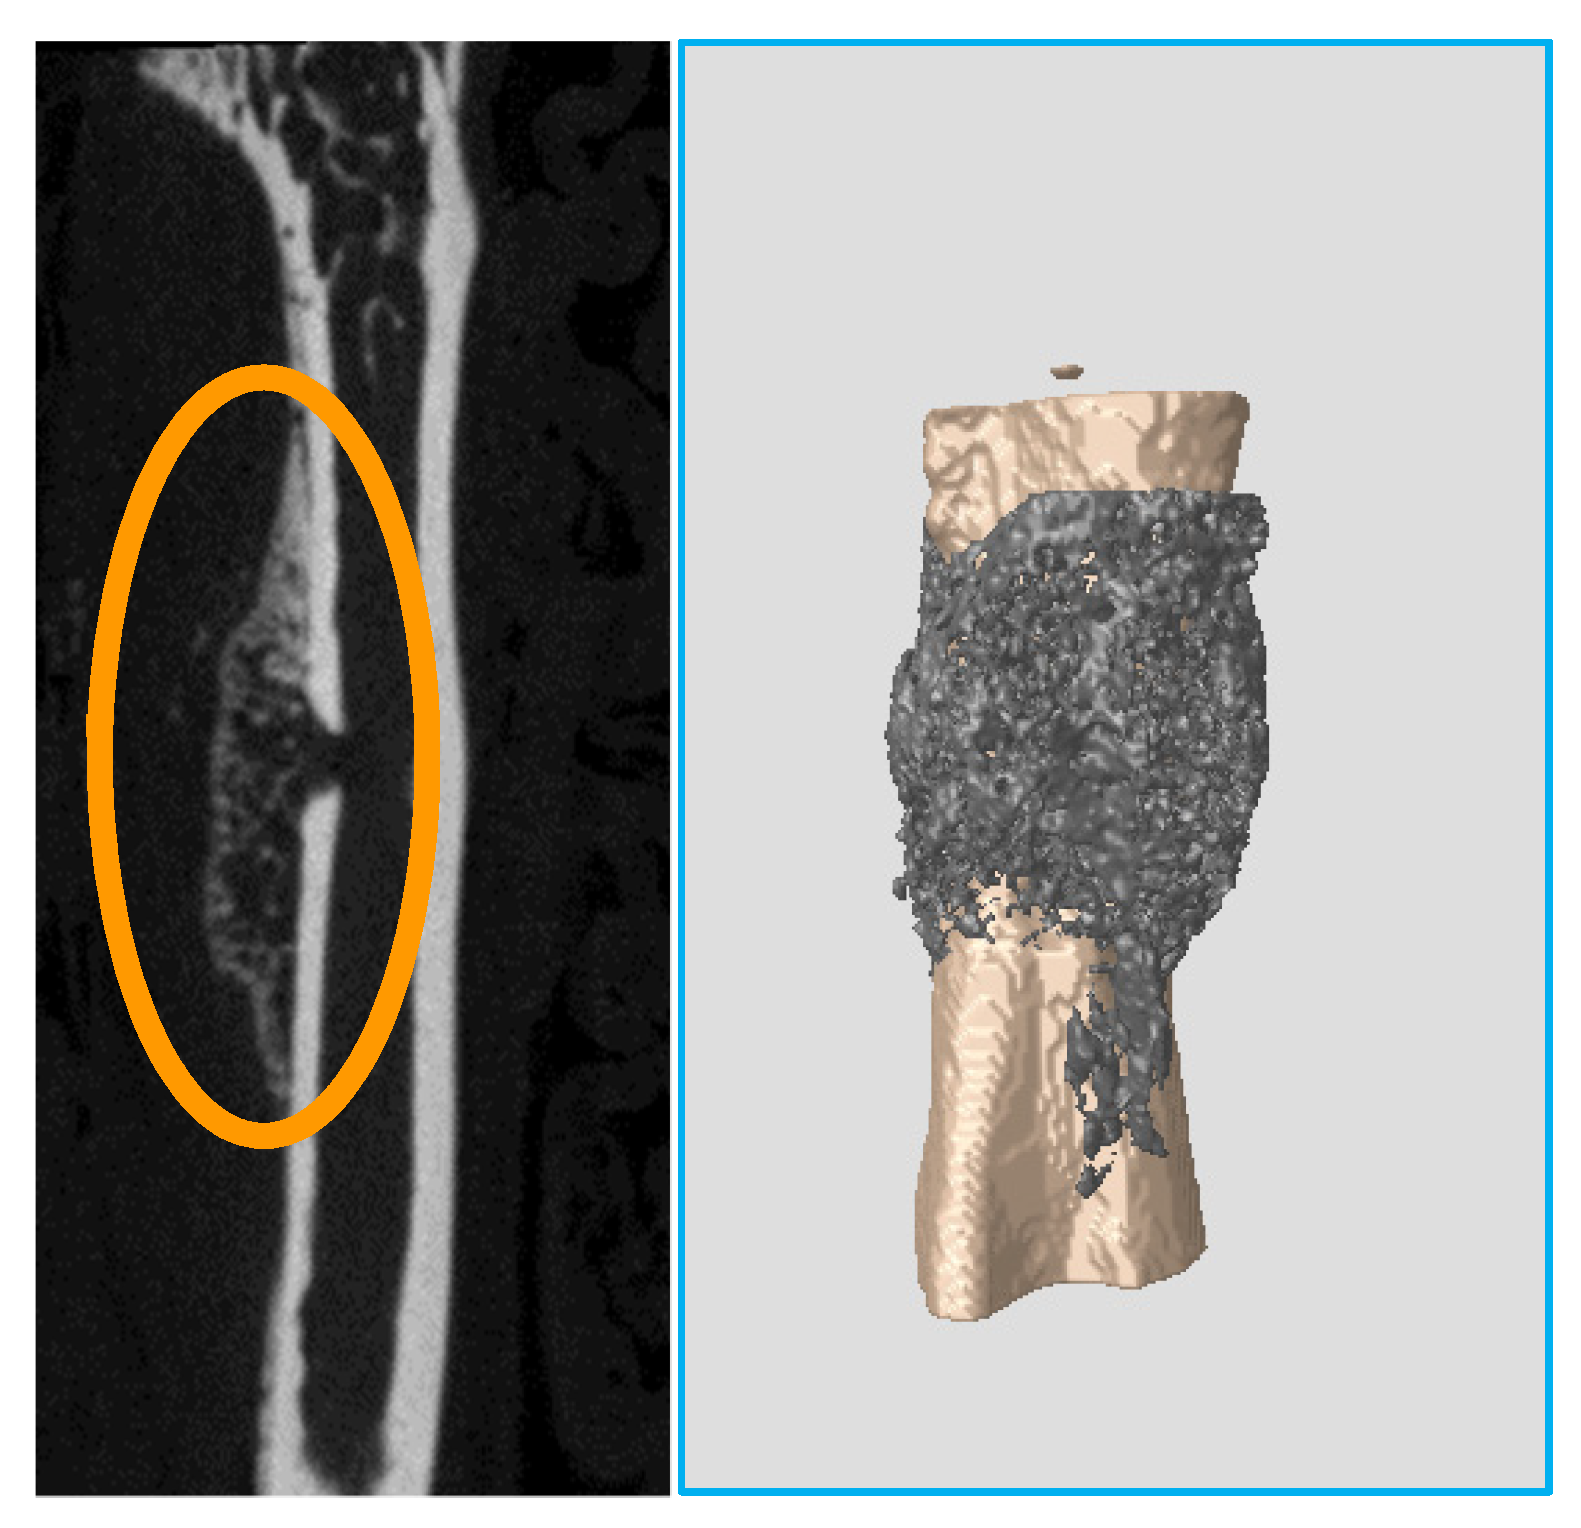

The quality of femur bone, lumbar vertebra, and hip joint of aging mice was evaluated in the present study. Male and female mice of a wide range of ages (7 to 80 weeks), strain Black6, were scanned using X-ray microtomography. Parameters such as mineral density were calculated to assess bone quality.

The parameter values and the images recorded reveal that bony and cartilage tissues remain in healthy condition until the age of 1 year. From this point, decay takes place in bone (osteoporosis) and joints (osteoarthritis). Mineral density of femur and vertebra trabecular bone decreases, while the free space between bone rods increases. The spongy architecture is maintained with wider gaps. The trabecular bone becomes less (Figure 1).

The cartilage covering the femoral head in hip joints mineralizes. It converts to a thick bony layer, losing the elastic properties of the chondral tissue (Figure 2). Osteoarthritis is installed. On the other hand, subchondral bone remains dense until the age of 80 weeks.

Figure 2.

(Left): 7 weeks (healthy) femoral head section. Outer cartilagenous layer is evident. (Right): 80 weeks (osteoarthritic) femoral head section. Cartilage has completely mineralized.